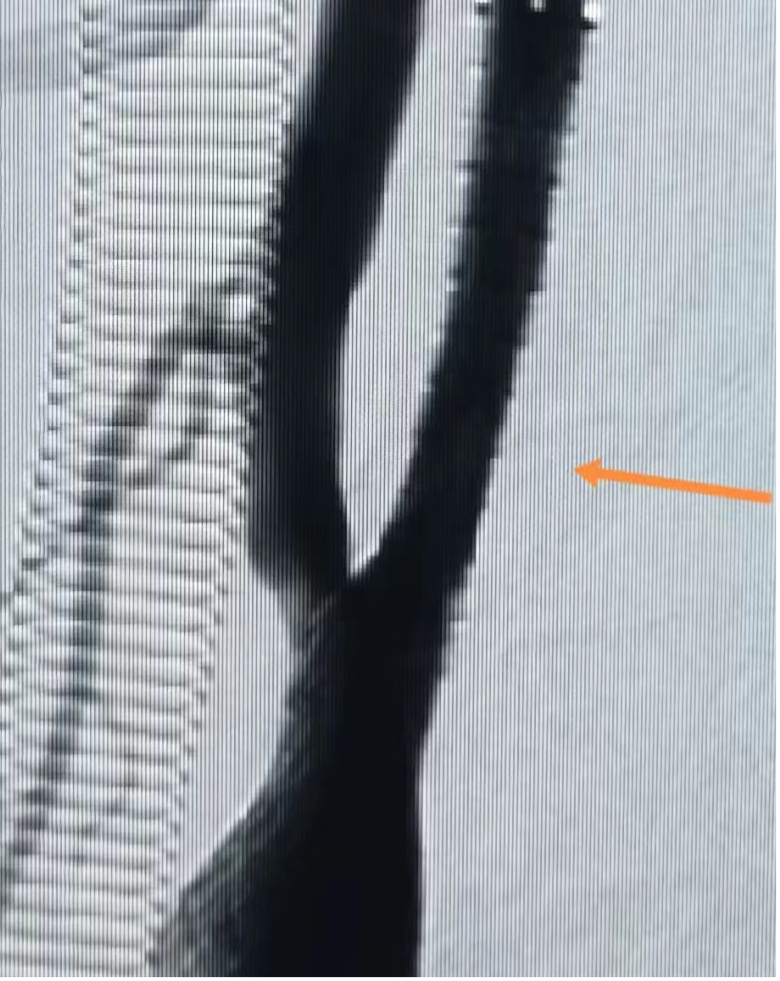

支架植入術(shù)后

術(shù)前,科主任袁玉麟積極協(xié)調(diào),做好充分準備。術(shù)前評估:患者平時有竇性心動過緩,心率在50—60次/分(正常75次/分左右),考慮術(shù)中可能出現(xiàn)心率下降,手術(shù)風(fēng)險高,擬在介入導(dǎo)管室、麻醉與圍術(shù)期醫(yī)學(xué)科多科協(xié)作下,行全麻下右側(cè)頸內(nèi)動脈起始段重度狹窄球囊擴張+支架置入術(shù)。術(shù)中球囊擴張時心率降至35次左右,給予阿托品應(yīng)用后好轉(zhuǎn)。由于患者血管狹窄嚴重、血管彈性差,植入支架后支架擴張不滿意;再次給予支架內(nèi)球囊二次擴張,二次擴張后顯示狹窄血管擴張滿意,遠端血流恢復(fù)正常。手術(shù)歷時約30分鐘順利完成。